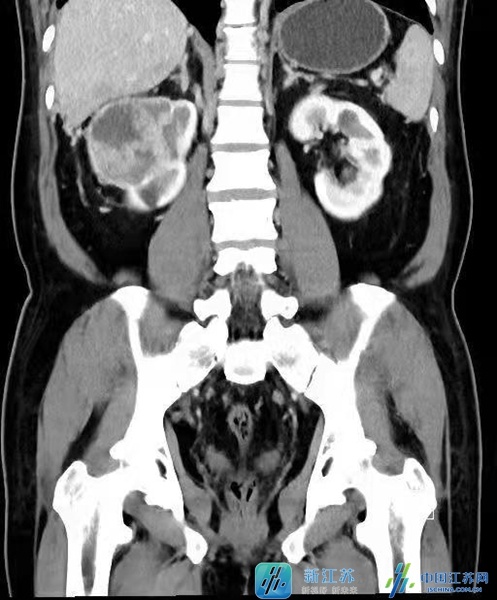

張先生今年58歲,平日裡身體一直較為健朗,但在今年9月的一次體檢中發現右腎長了一枚腫瘤,這可把張先生急壞了。張先生及家人在多方打聽後,慕名來到江蘇省人民醫院李傑教授門診就診。李傑教授在仔細看完他的影像學檢查後發現,張先生不僅右腎長了腫瘤,且腫瘤侵入右腎靜脈及下腔靜脈形成了癌栓,更糟糕的是癌栓上緣已右心房,甚至部分已透過二尖瓣進入右心室,瘤栓一旦脫離,張先生的隨時都有生命危險,此時情況非常危險,需要立即入院接受手術治療。雖然手術風險極大,但是如手術成功,張先生可獲得良好的預後。張先生及家人雖然很緊張,但更堅信李傑教授團隊的水平和能力,決定立即入院接受手術。

由於張先生的右腎腫瘤巨大,癌栓的位置又已經到達了心房,手術過程中稍有不慎,就會出現心臟驟停以及血管破裂的情況,李傑教授在同心髒大血管外科、麻醉與圍術期醫學科、手術室、重症醫學科、輸血科多方共同探討評估了張先生病情,並與張先生充分溝通後,定下了於開放下行腎癌根治術以及體外迴圈下右心房、腔靜脈癌栓取出術的手術計劃。

李傑教授介紹指出:伴有下腔靜脈癌栓的腎癌根治加癌栓取出手術是泌尿外科難度最高的手術之一,根據國外報告,圍手術期的死亡率為10%。根據美國梅約醫學中心的分類法,可將癌栓分為以下五級:0級:癌栓侷限於腎靜脈內;I級:癌栓侵入下腔靜脈內,癌栓頂端距腎靜脈開口處≤2cm;II級:癌栓侵入下腔靜脈內,距腎靜脈開口處>2cm;III級:癌栓生長達肝內下腔靜脈水平,膈肌以下;IV級:癌栓侵入膈肌以上下腔靜脈內。癌栓級數越高,手術的風險與難度就越大。然而多數情況下,病人無法靠感覺來察覺到腫瘤以及癌栓,因此每年定期做一次全面體檢是非常重要的。